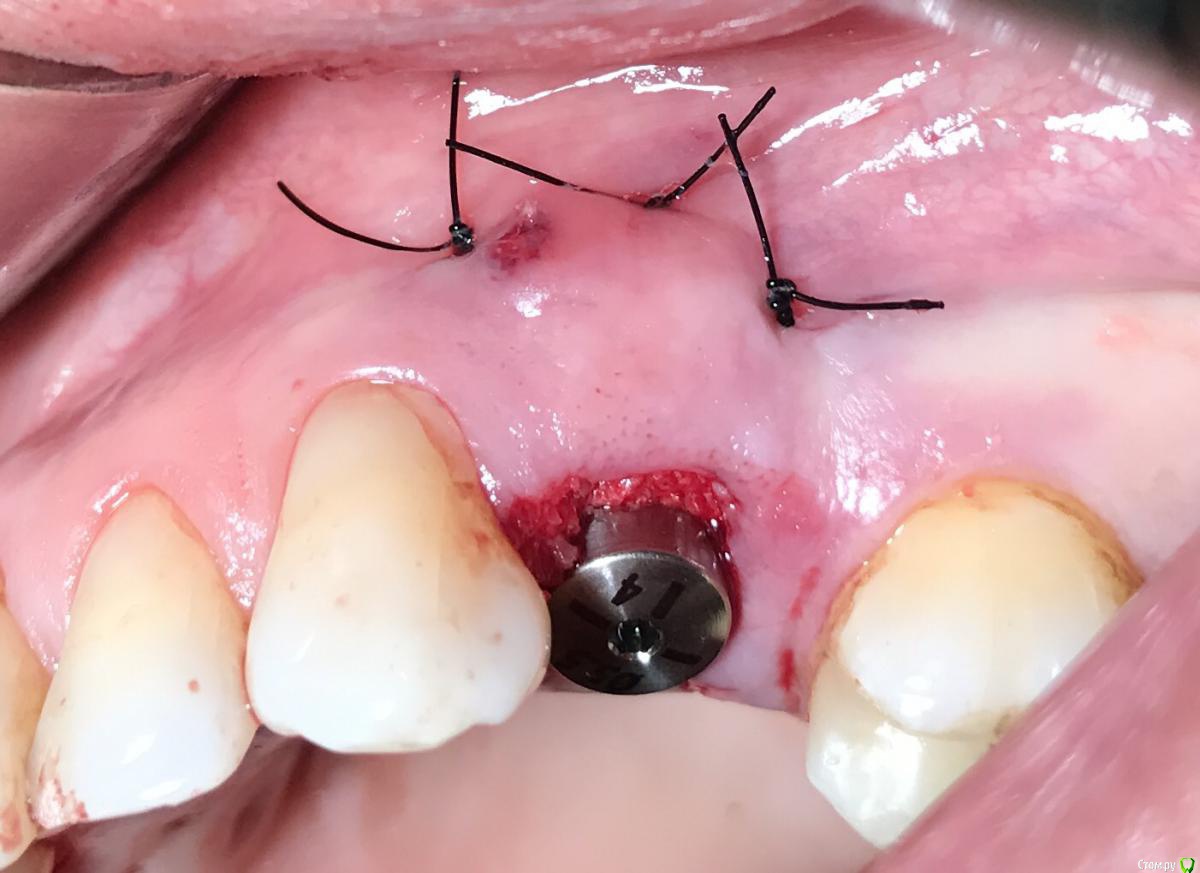

колесников Опубликовано 25 февраля, 2017 Поделиться Опубликовано 25 февраля, 2017 Здравствуйте коллеги! Представляю вашему вниманию этот клинический случай.В ноябре 2016 обратилась пациентка с жалобами на выпадение ортопедической конструкции в обл 24. Объективно: корни 24 не состоятельны. ,на десневом крае в проекции 24 свищевой ход с гнойным отделяемым.На КТ резорбция вестибулярной компактной пластинки и деструкция костной ткани в области щёчного корня.Приняв во внимание крайне негативное отношение пациентки к каким бы то ни было хирургическим вмешательствам и высоким эстетическим требованиям,было решено пойти на немедленную имплантацию .Снимки в день вмешательства,через 7,14 дней и 3мес.Имплант Astra tech profile 4.5х11мм. Сст с бугра вестибулярно. Вместо графта губки Коллапола (не вспомню причину,либо не было в наличии,либо отказ пациента). 15 Ссылка на комментарий

колесников Опубликовано 26 февраля, 2017 Автор Поделиться Опубликовано 26 февраля, 2017 Да,можно было ещё на 1мм притопить,и конечно графт вестибулярно оставить,но это стало понятно только сейчас. При постановке имплант был заглублен на 3 мм, посчитал что этого достаточно, но резорбция случилась больше планируемой. Первоначально планировалась нагрузка через 5 сут ,но ортопед позднее отказался от этой идеи. Думал заменить фдм на зебру,но пациентка пропала на 3 мес... Как получилось,так получилось. Торк был 35н/см,как обычно на астре. Ссылка на комментарий

колесников Опубликовано 12 июня, 2017 Автор Поделиться Опубликовано 12 июня, 2017 Контрольное кт спустя 3 мес. Откуда-то наросло 2мм у шейки. Ссылка на комментарий

Doctor Vlad Опубликовано 13 июня, 2017 Поделиться Опубликовано 13 июня, 2017 Откуда-то наросло 2мм у шейки. да видимо графт был, причем не коллапон коллагеновый а костная стружка, даже по первым снимкам после операции там чтото рыхлое торчит. Ссылка на комментарий